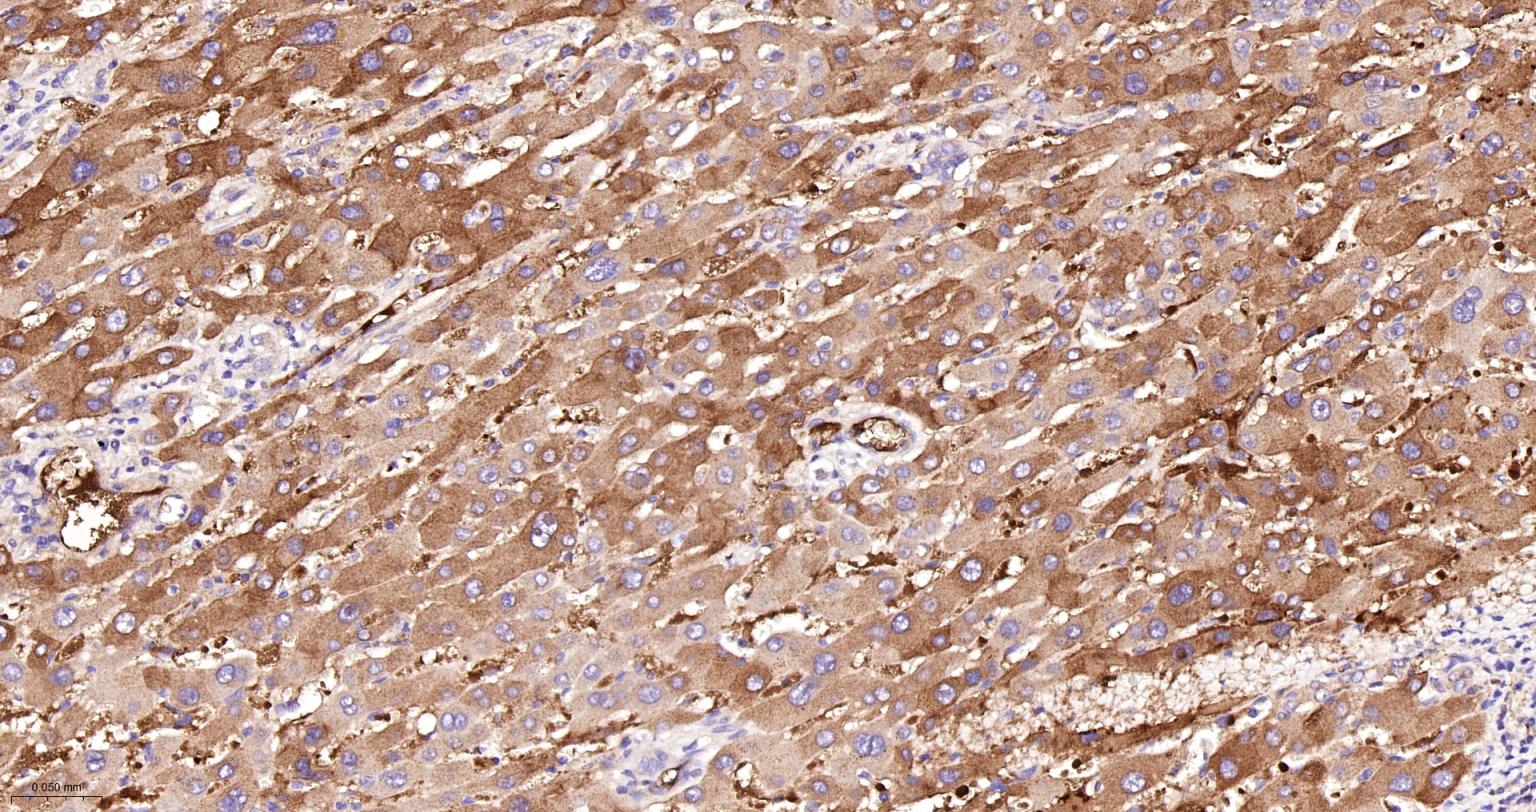

Paraformaldehyde-fixed, paraffin embedded Human Liver; Antigen retrieval by boiling in sodium citrate buffer (pH6.0) for 15 min; The section was incubated with Factor X Monoclonal Antibody, Unconjugated (bsm-61666R) at 1:200 overnight at 4°C, followed by conjugation to the bs-0295G-HRP and DAB (C-0010) staining.